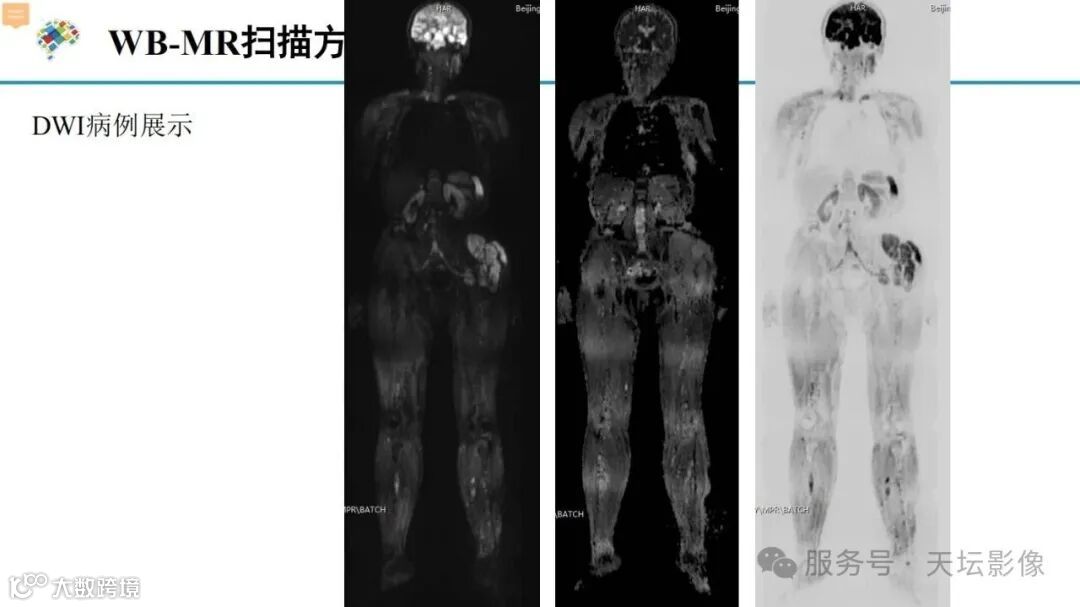

天坛扫描方案!NF1相关丛状神经纤维瘤推荐MR扫描方案